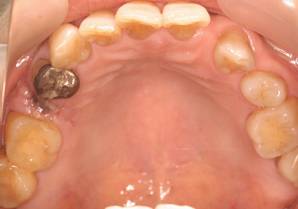

術前。すべての歯が歯周病の末期状態でブリッジ全体がうごいて噛めないとの訴え。右上の犬歯が腫れていました

固定式のブリッジが入っていましたが歯周病で動いています

下顎前歯部には歯石の沈着がみられます

術前パノラマレントゲン写真。根の周りが黒くなり、骨がなくなっていることがわかります